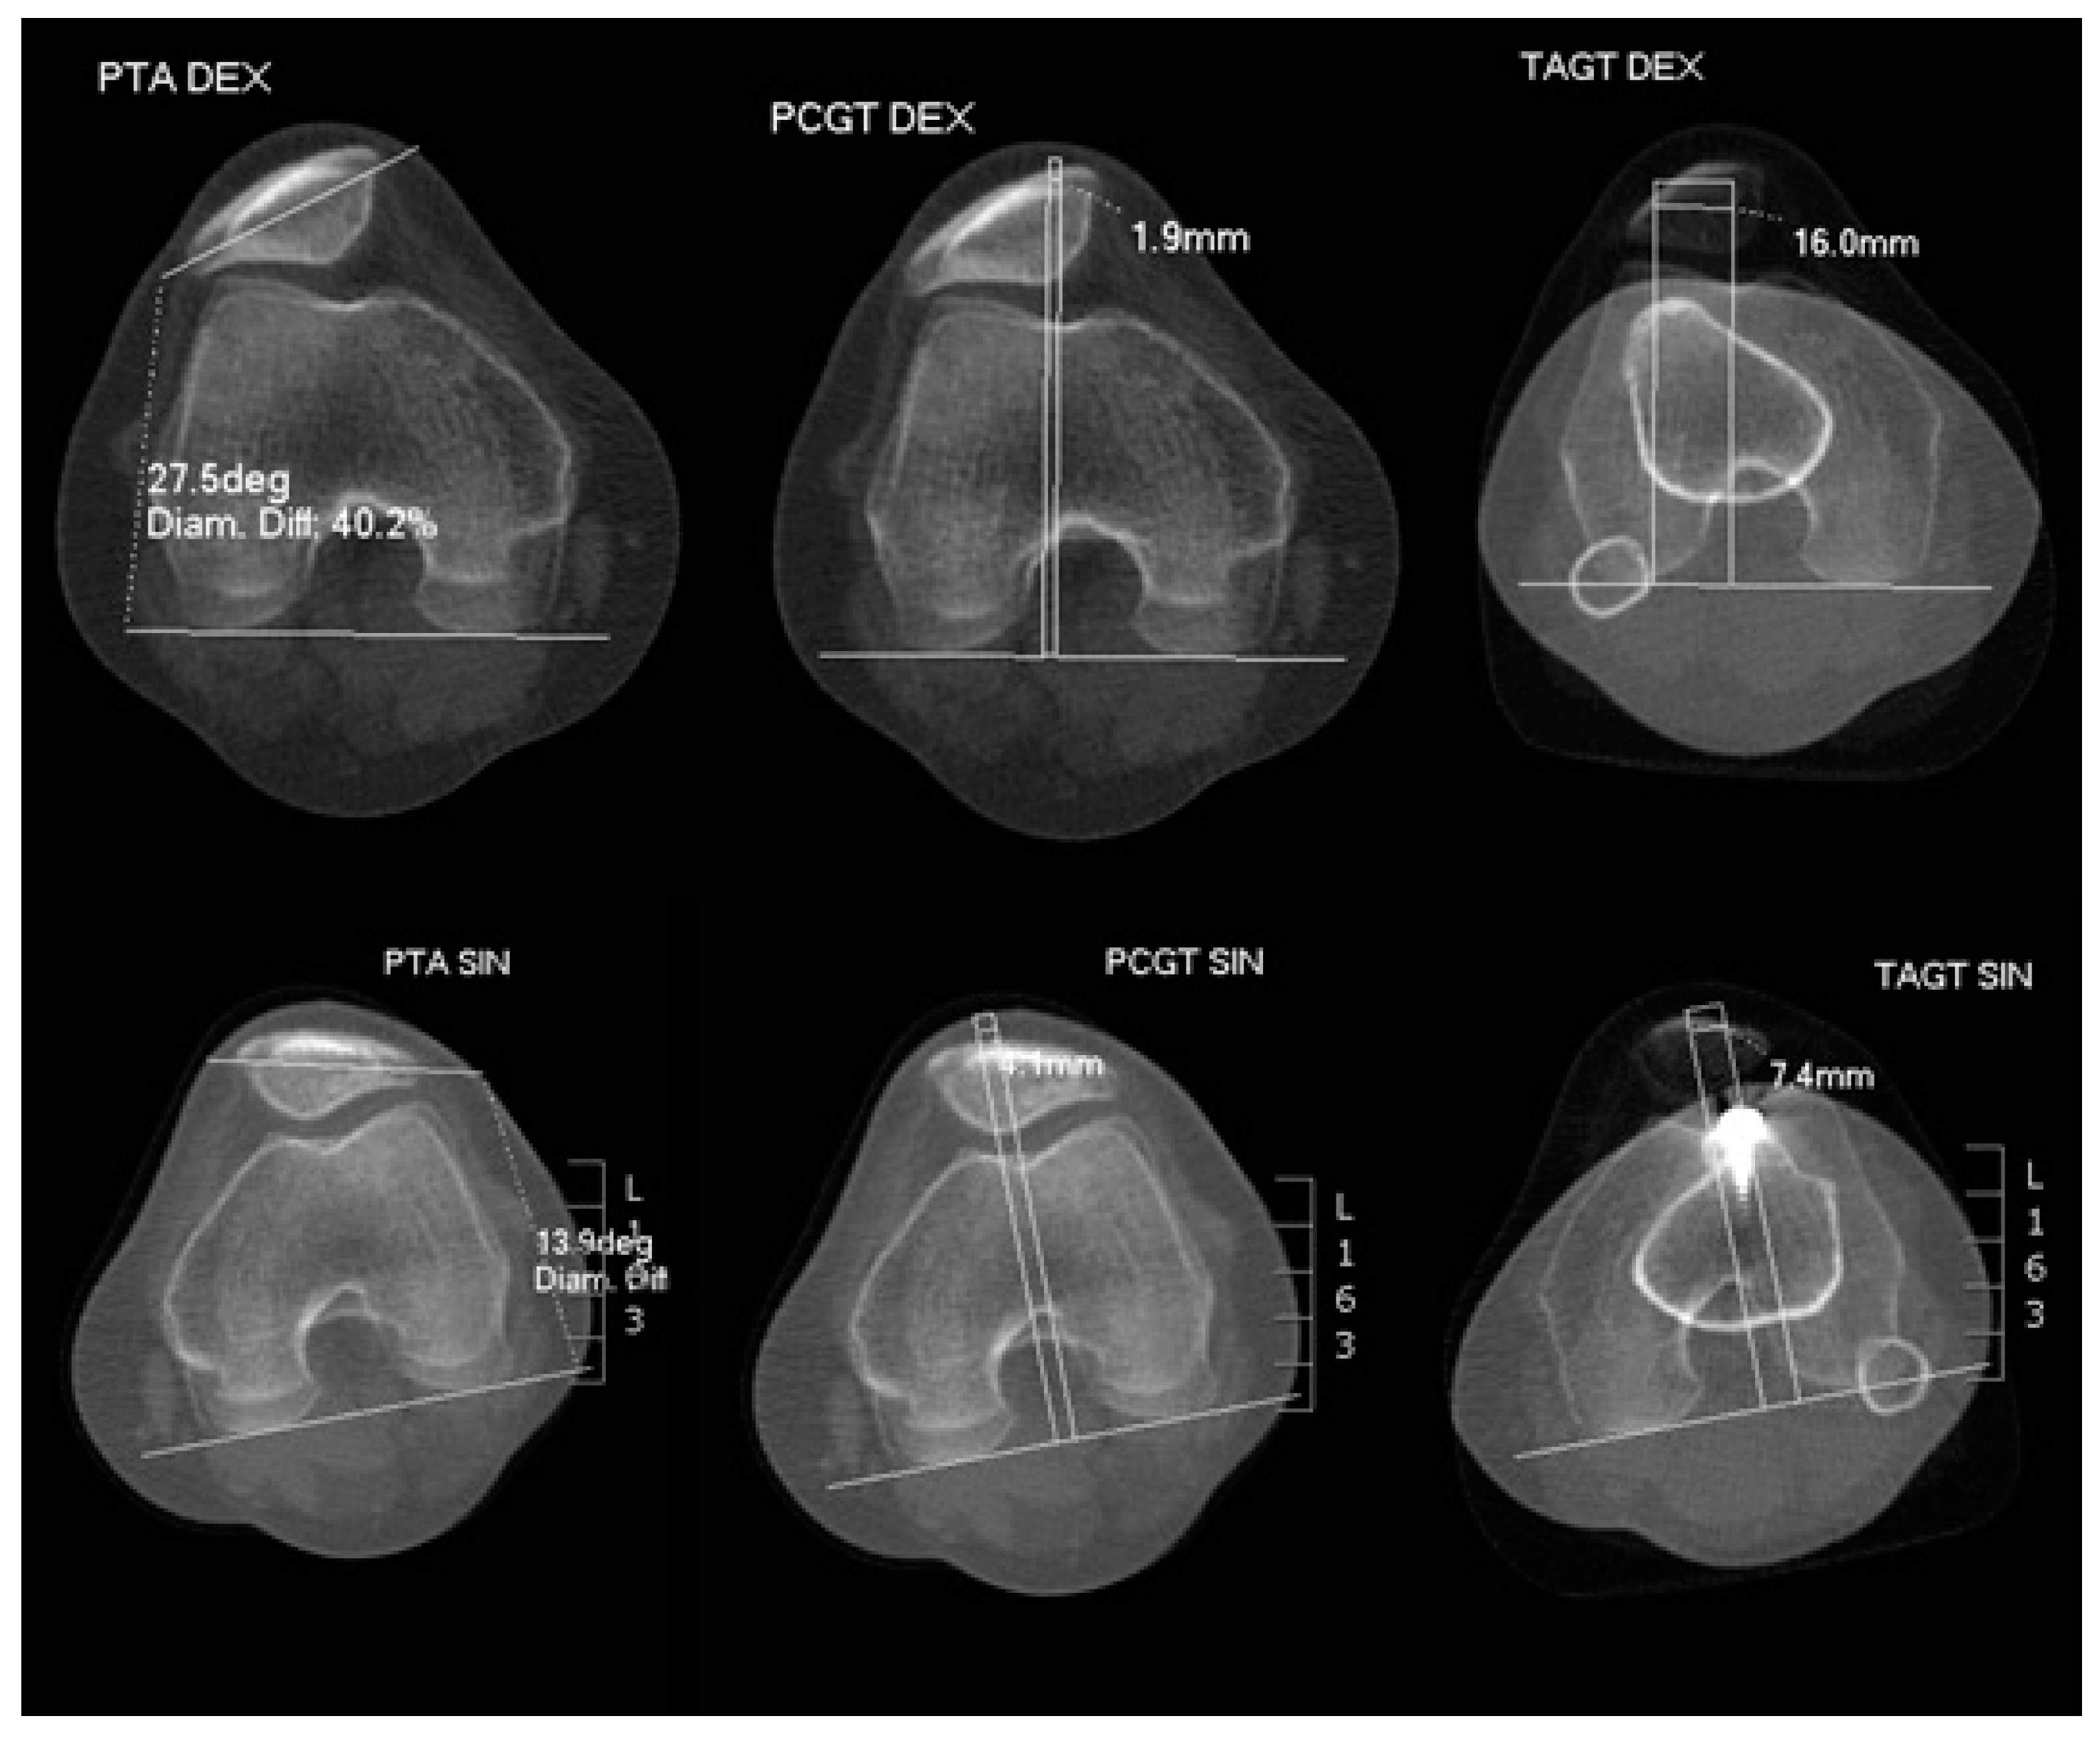

Medial Patellofemoral Ligament and Lateral Patellofemoral Ligament Reconstruction after Tibial Tuberosity Transposition in a Young Woman with Patellar Instability